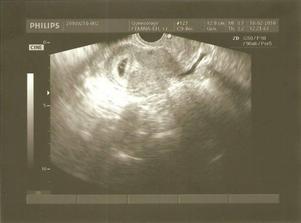

18.2. 2010 - prvé vyšetrenie u pani doktorky, aj sa tešíme ale sa aj obávame...tak pani doktorka nám tehotenstvo potvrdila a dala nám aj obrázok malého zázraku....